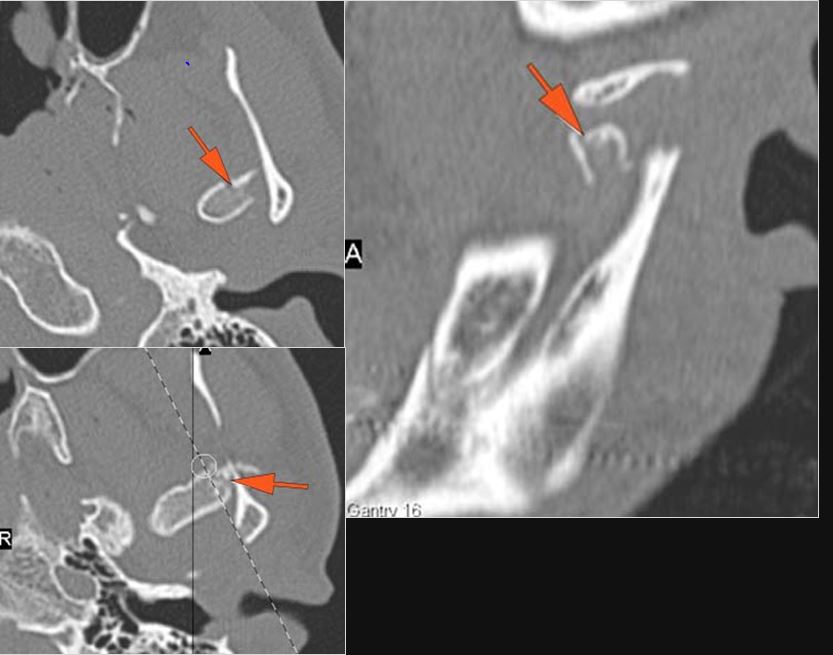

The mesial naso-orbito-ethmoid complex is fractured. Specifically, there is bony injury of the nasal bones or the frontal process of the maxilla and the medial walls of the orbit are abnormal.

There is injury of the ethmoid complex. Specifically, the ethmoid roof, olfactory fossa and the cribriform plate are fractured and/or significantly dehiscent.